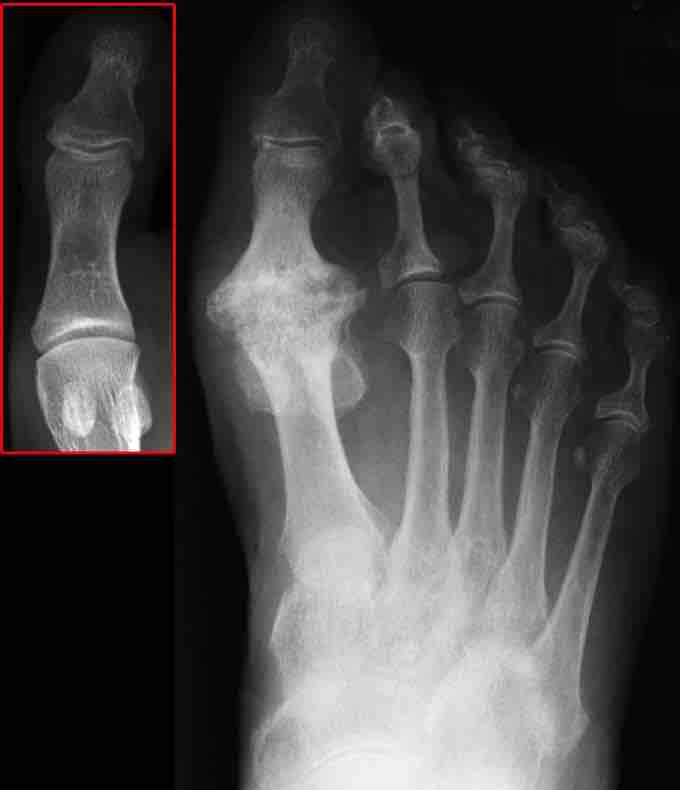

Osteoarthritis is the degenerative inflammation of the joints, and is the leading cause of disability in people over the age of 55. Osteoarthritis is typically caused by mechanical stress on the joints, resulting in chronic inflammation leading to the loss of cartilage . Osteoarthritis affects the protective cartilage of the joint, causing it to wear down over time, exposing the bone underneath. The bones of the joint then rub together during movement, causing pain and stiffness. As a result of decreased movement secondary to pain, regional muscles may atrophy, and ligaments may become more lax. Osteoarthritis becomes more common as people age, due to increased mechanical stress on the joints.

X-ray image of osteoarthritis of the big toe. The red box shows the normal joint.